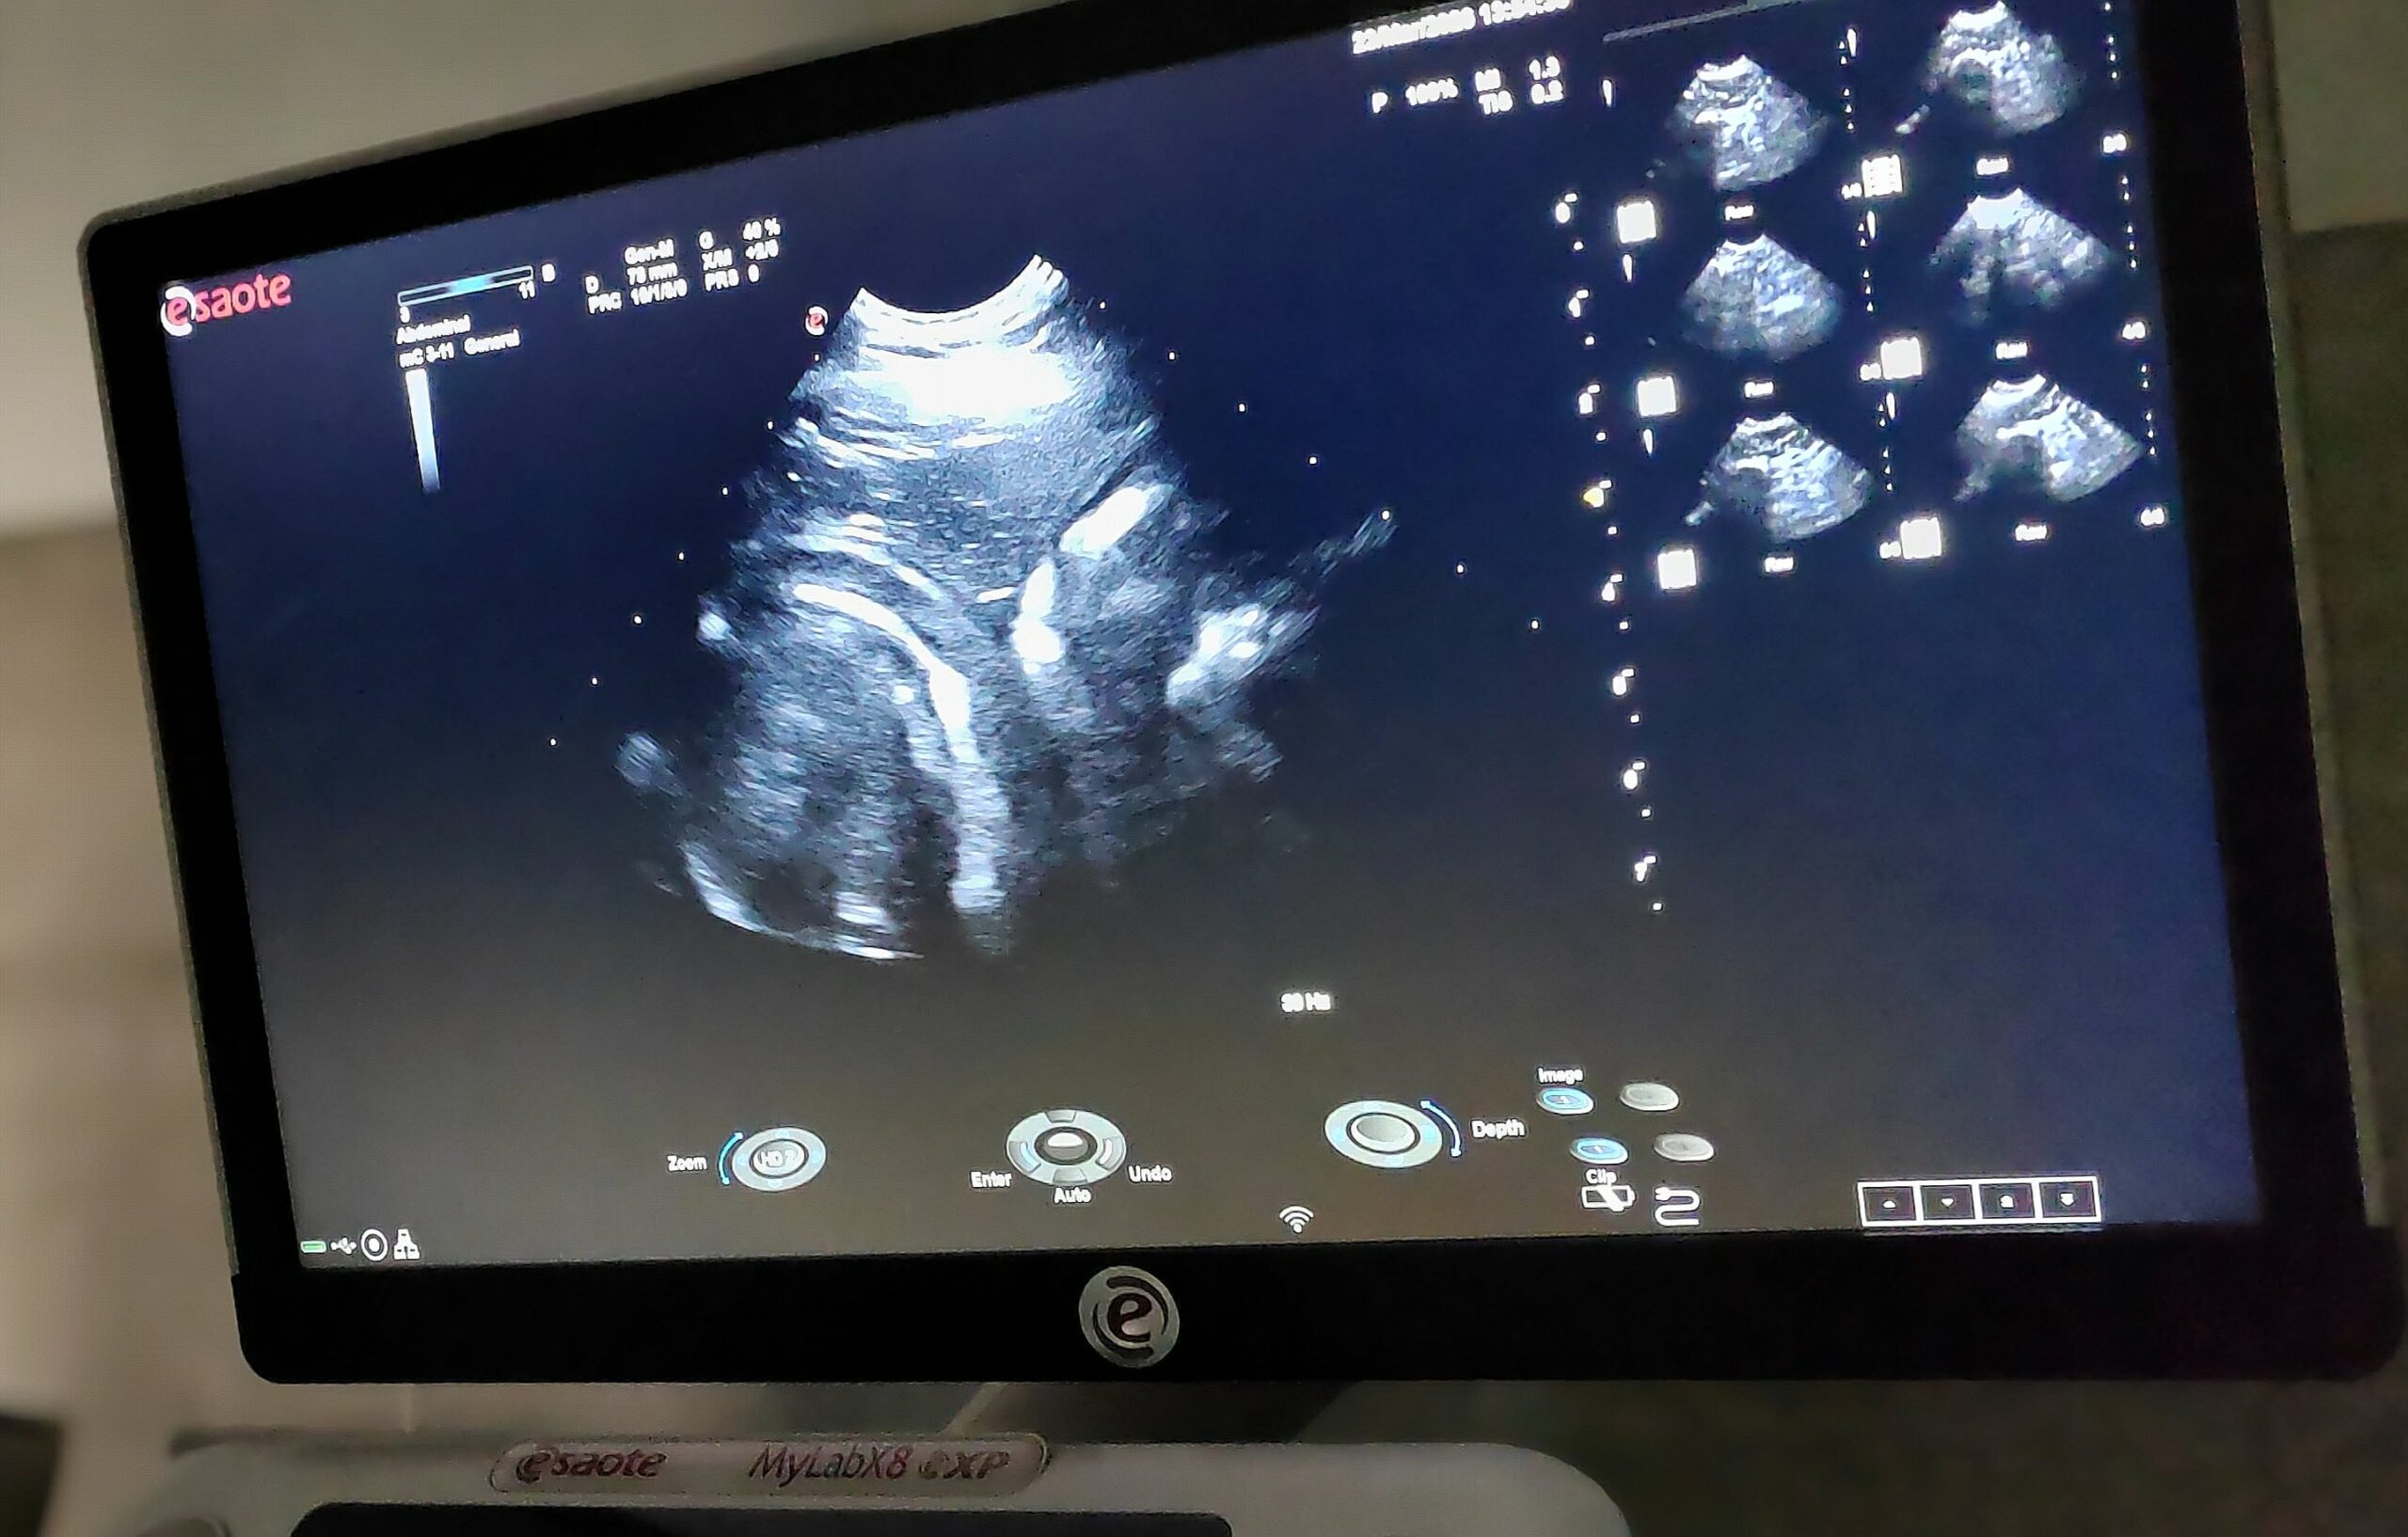

Sono 55. den

Kontrolní sono v 55. dni potvrdilo, že se štěňátka mají skvěle a krásně prospívají. Jsou už plně…